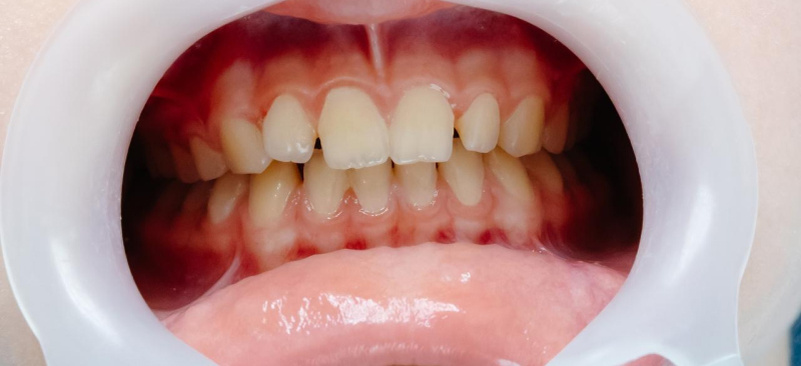

Признаки

• понижение уровня десны, из-за чего оголяется значительная часть зуба, он становится более чувствительным;

• оголение зубного корня может сделать улыбку менее привлекательной, а если атрофия выражена сильно, зубы выглядят непропорционально высокими и видна желтоватая часть зуба (корень);

• увеличение чувствительности зубов из-за повышенной реакции эмали к перепадам температуры (горячее или холодное) и химическим веществам (кислым или острым продуктам);

• развитие кариеса из-за оголённого корня зуба. Заметно появление гнойных выделений у шейки кости;

• дискомфорт, подвижность зубов и болезненность чаще всего появляются при приёме пищи.